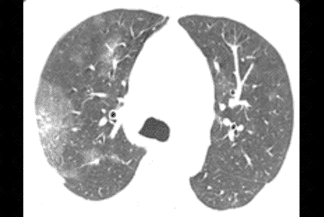

Descrição das figuras 1, 2 e 3: Tomografia computadorizada de tórax no momento da admissão. Esparsas opacidades em vidro fosco bilaterais, com envolvimento de mais de um lobo pulmonar e com distribuição predominantemente periférica. Em associação às áreas em vidro fosco, pode ocorrer ainda espessamento dos septos interlobulares, caracterizando o padrão de pavimentação em mosaico.

• Opacidades em vidro fosco, bilaterais, acometendo a maioria dos lobos pulmonares (acometimento multilobar), assimétricas e com predomínio na periferia dos pulmões;

• Em associação às áreas em vidro fosco, pode coexistir o espessamento dos septos interlobulares, caracterizando o padrão de pavimentação em mosaico;